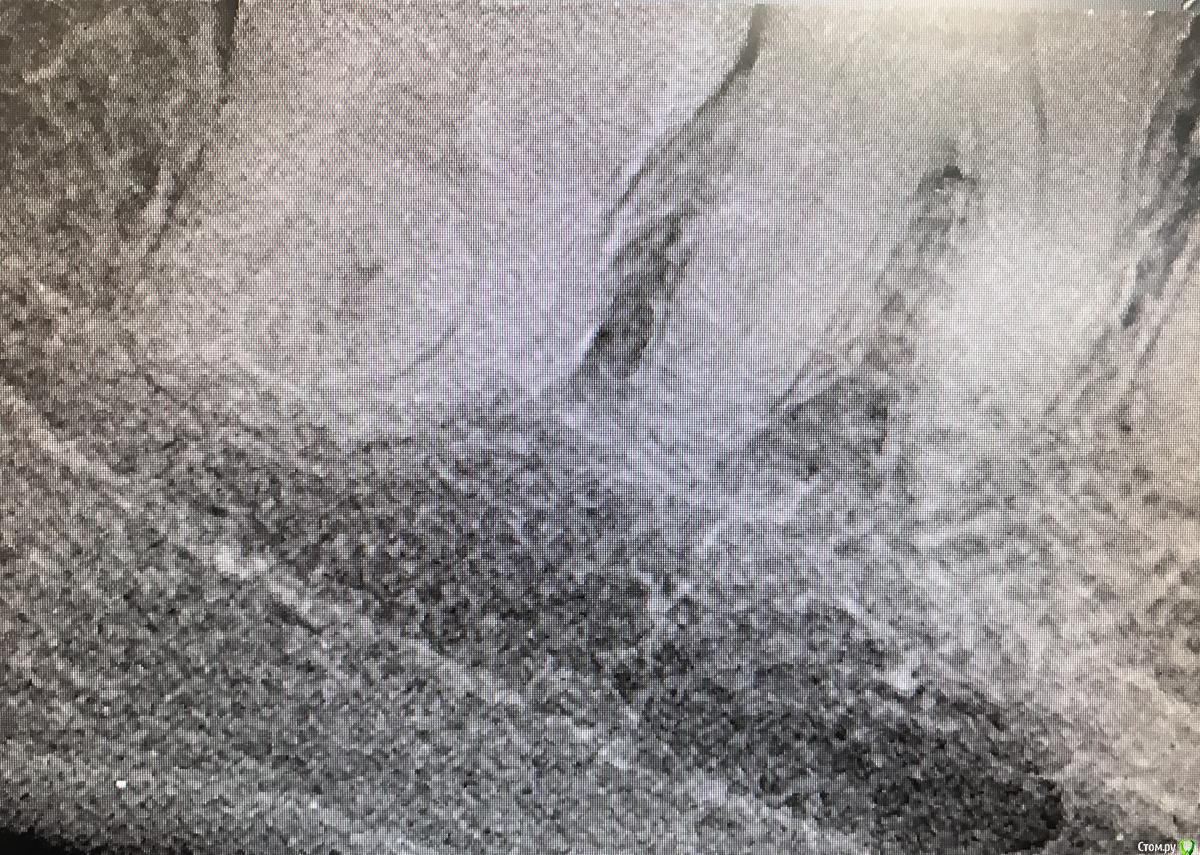

колесников Опубликовано 26 марта, 2017 Автор Поделиться Опубликовано 26 марта, 2017 (изменено) Вид через неделю. Швы удалены. Пациент как ни странно жив. Боли не испытывал ,3 дня был отек. Снимок "до". Изменено 26 марта, 2017 пользователем колесников Ссылка на комментарий